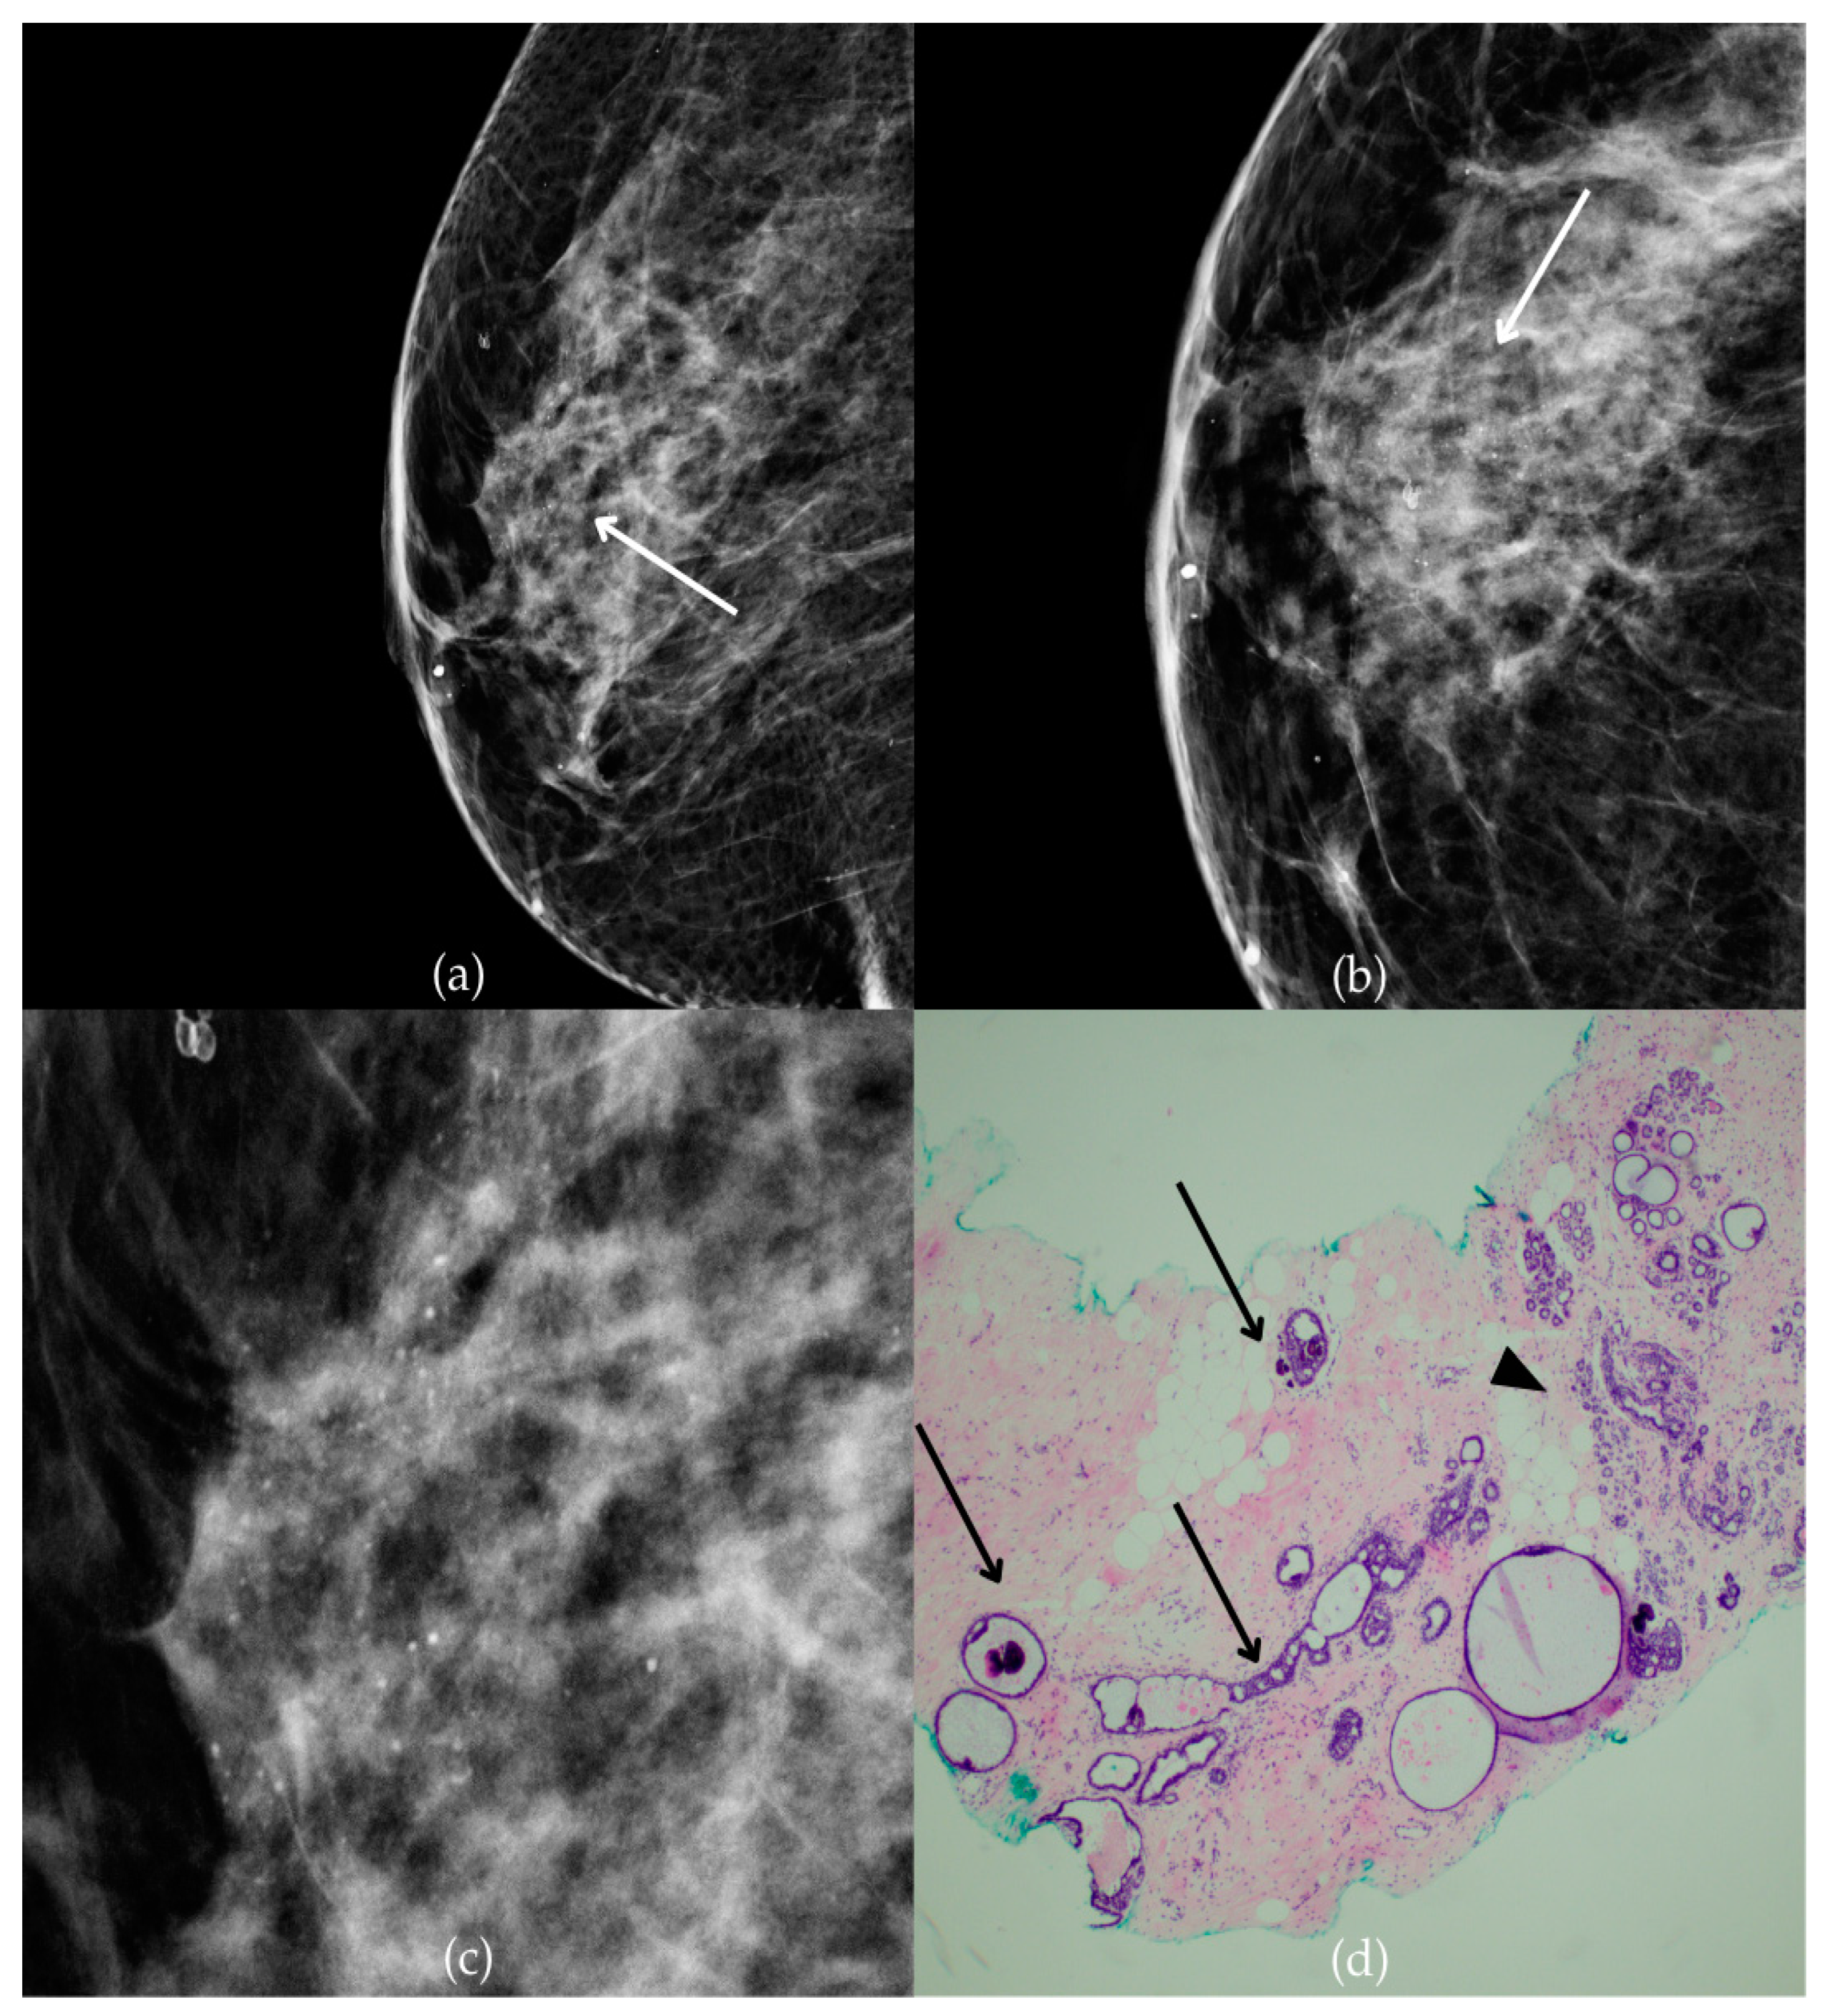

Figure 1 presents mammographic and histopathological images of a 74-year-old patient. The mammogram of the right breast shows grouped coarse heterogeneous and fine pleomorphic calcifications in the upper outer quadrant, classified as a BI-RADS 4 finding. Given the suspicious nature of these findings, a biopsy was performed. A tissue analysis confirmed the presence of a DCIS (category B5a). The patient underwent quadrantectomy, and the postoperative pathology confirmed the diagnosis. At the most recent follow-up, conducted one year after the initial diagnosis, the US examination was classified as BI-RADS 2, indicating benign findings.

Figure 1.

Ductal carcinoma in situ (DCIS). (a) Mediolateral oblique (MLO) mammography view; (b) craniocaudal (CC) mammography view of the right breast showing grouped coarse heterogeneous and fine pleomorphic calcifications (marked with arrows) in the upper outer quadrant. (c) Magnified mammographic image of grouped coarse heterogeneous and fine pleomorphic calcifications. (d) The histopathological image of the biopsy sample reveals the characteristic features of DCIS (HE staining; 40× magnification).